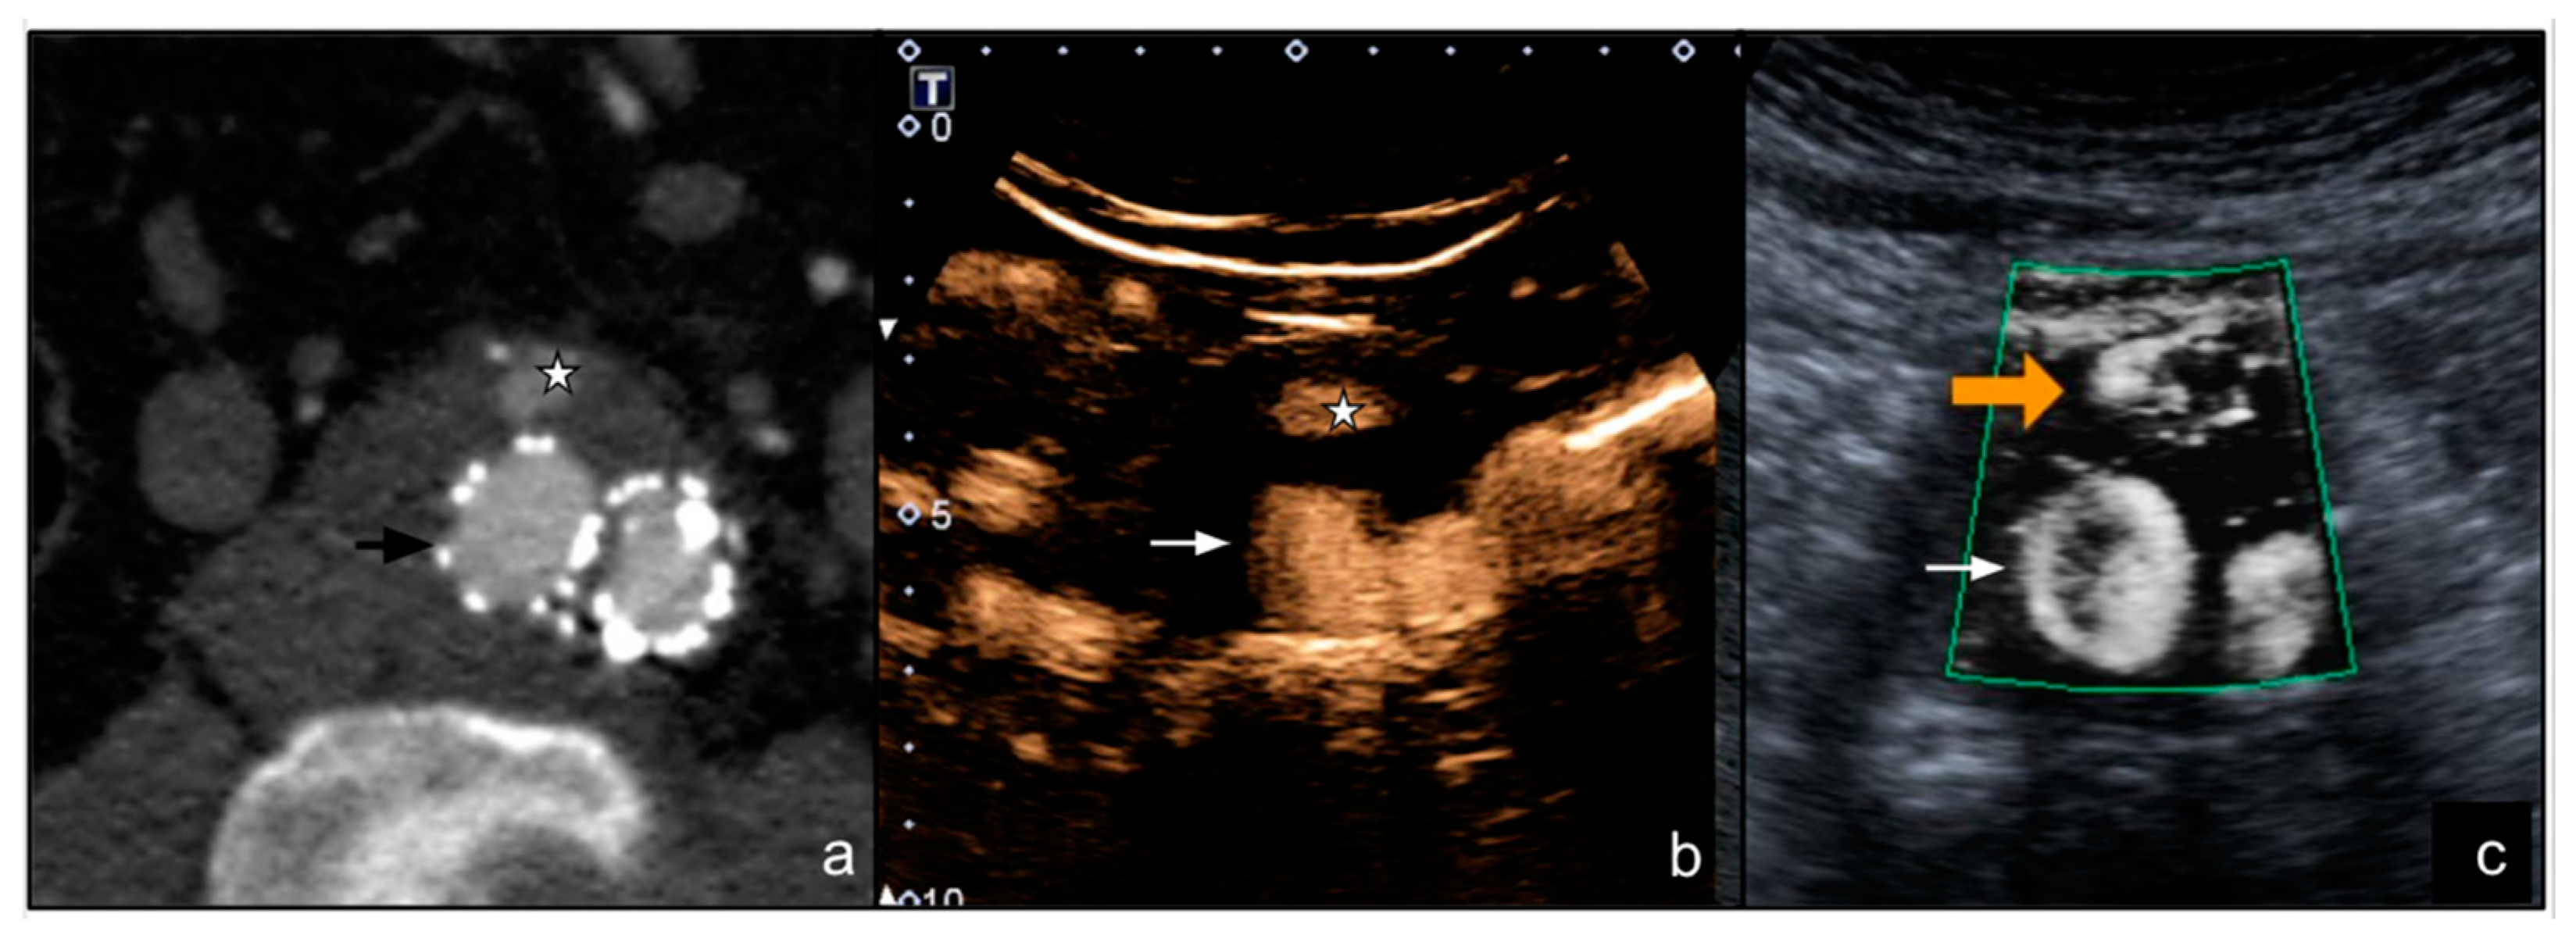

- Cantisani, V.; David, E.; Ferrari, D.; Fanelli, F.; Di Marzo, L.; Catalano, C.; Benedetto, F.; Spinelli, D.; Katsargyris, A.; Blandino, A.; et al. Color Doppler Ultrasound with Superb Microvascular Imaging Compared to Contrast-Enhanced Ultrasound and Computed Tomography Angiography to Identify and Classify Endoleaks in Patients Undergoing EVAR. Ann. Vasc. Surg. 2017, 40, 136–145. [Google Scholar] [CrossRef] [Green Version]

- Gabriel, M.; Tomczak, J.; Snoch-Ziółkiewicz, M.; Dzieciuchowicz, Ł.; Strauss, E.; Oszkinis, G. Comparison of Superb Micro-Vascular Ultrasound Imaging (SMI) and Contrast-Enhanced Ultrasound (CEUS) for Detection of Endoleaks After Endovascular Aneurysm Repair (EVAR). Am. J. Case Rep. 2016, 17, 43–46. [Google Scholar] [CrossRef] [PubMed] [Green Version]